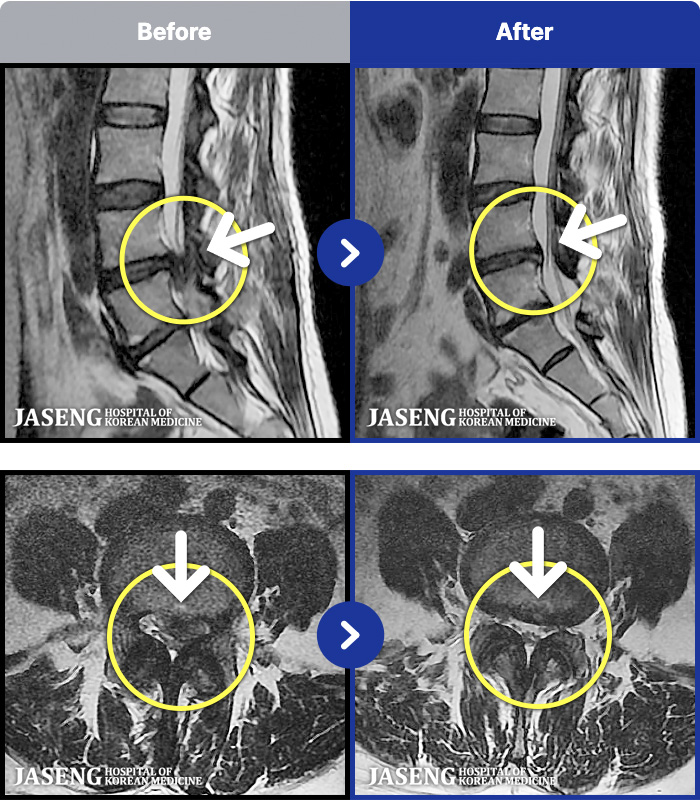

ȯںп Ǹ ǿ ԿǾ, ο ġ ۿ Ƿ ġḦ Ͻñ ٶϴ.